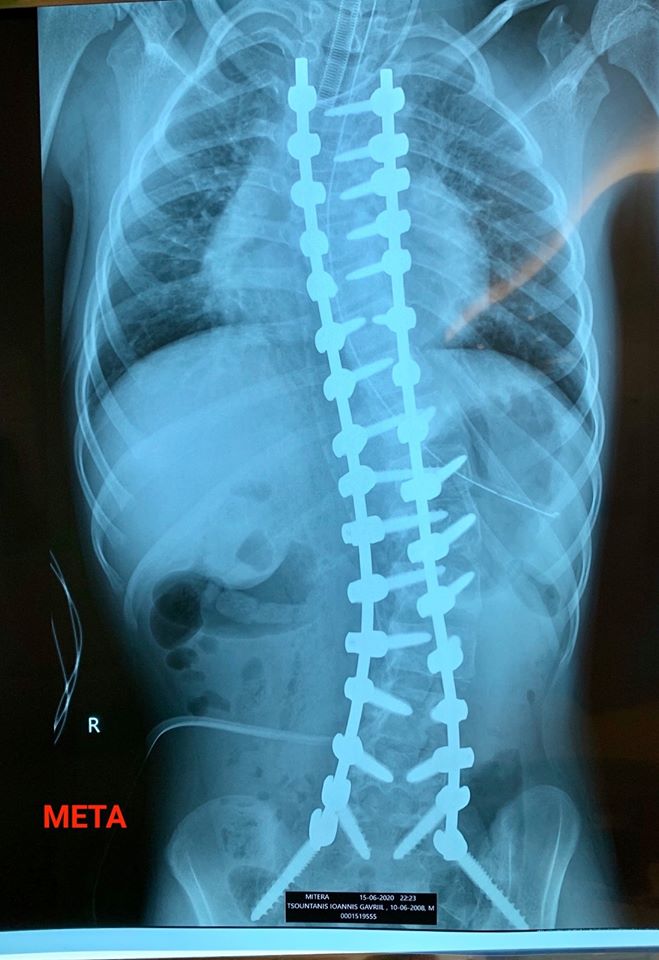

Αμέτρητοι είναι οι φίλοι που μας ευχήθηκαν και μας έδωσαν κουράγιο σε μια δύσκολη περίοδο για το Γιαννάκη μας. Ήταν ο μήνας που έπρεπε επιτέλους να μπούμε στο χειρουργείο για ολική σπονδυλοδεσία. Λόγω της προχωρημένης και ιδιότυπης σκολίωσης τα πράγματα ήταν εξαιρετικά δύσκολα και ειδικά για ένα παιδί ΑΜΕΑ με βεβαρημένο ιατρικό ιστορικό.

Όμως, όλα πήγαν κατ’ ευχήν! Έχουμε επιστρέψει στο σπίτι μας, νικητές. Η αποθεραπεία μπορεί να πάρει καιρό, αλλά το πείσμα για ζωή του Γιαννάκη είναι η δύναμη του. Κι αυτό είναι το πιο σημαντικό.